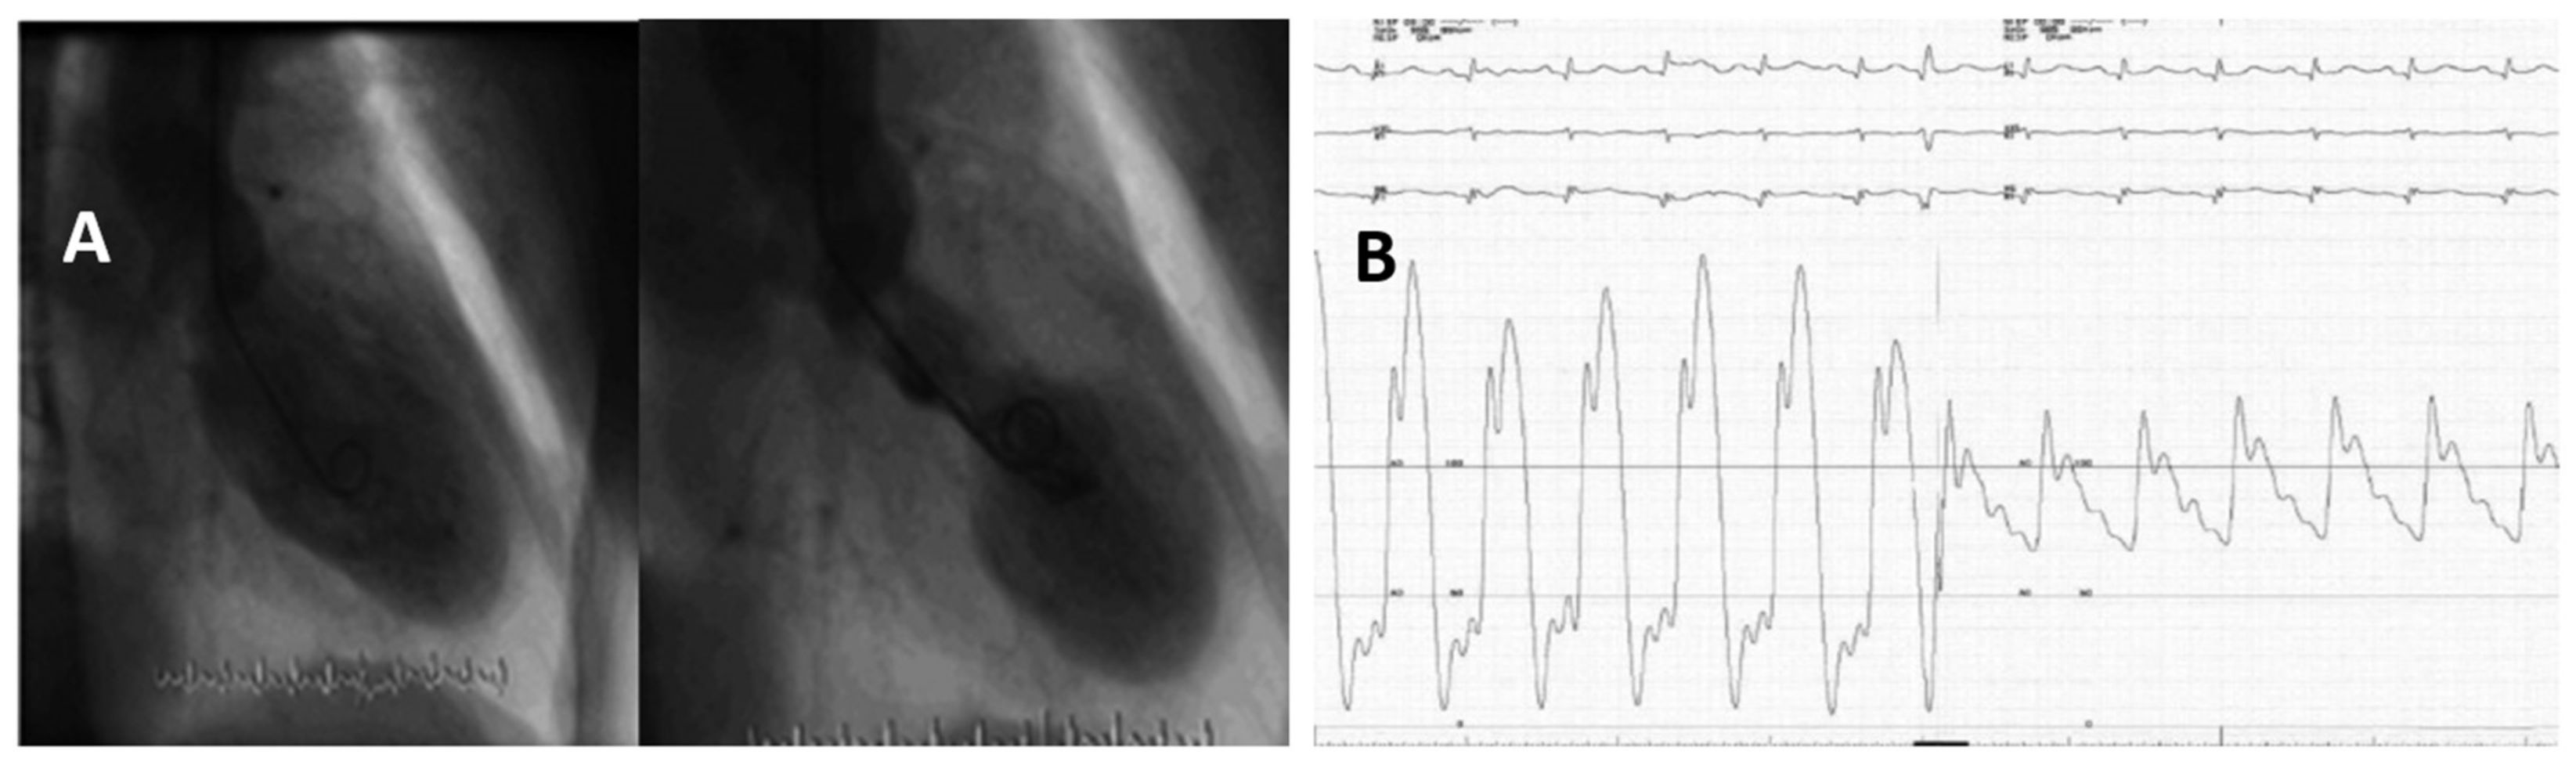

3.14. Heart Rupture in Patients with TTS

3.16. Ventricular Arrhythmias in Patients with TTS

- Kumar, S.; Kaushik, S.; Nautiyal, A.; Choudhary, S.K.; Kayastha, B.L.; Mostow, N.; Lazar, J.M. Cardiac rupture in takotsubo cardiomyopathy: A systematic review. Clin. Cardiol. 2011, 34, 672–676. [Google Scholar] [CrossRef] [PubMed]